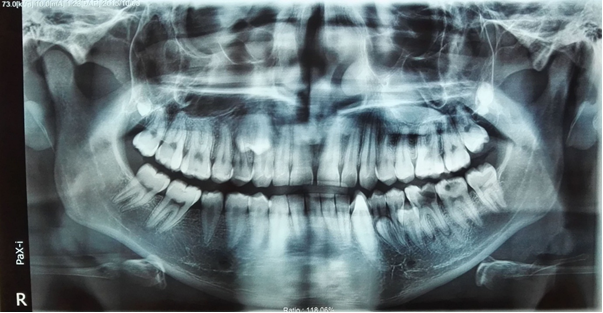

A 19-year-old Iranian male presented for an initial dental examination which involved taking panoramic radiograph. The patient had no complaint of pain, no sign of infection and was in good general health, with no other alterations. The patient has the history of bilateral ulnar polydactyly that was removed operatively at his early childhood. This bilateral ulnar polydactyly was not associated with syndactyly and polydactyly of the feet. On intraoral examination there were no abnormalities in the shape or size of the teeth or the relationship between the patient’s dental and chronological age. And also, there was no any other specific oral finding and relevant familial history of dental abnormalities. On clinical examination no craniofacial and skeletal anomaly related to supernumeraries (e.g. craniosynostosis, absence of clavicles, hypertelorism, ear deformity, etc.) was detected. The panoramic radiograph showed the presence of ten supernumerary teeth in all four quadrants (Fig. 1). On clinical examination it was found that all the permanent teeth including the third molars had erupted and the tooth number 36 had been extracted. CBCT (cone beam computed tomography) of the mandible and maxilla was taken to confirm the location of the supernumerary teeth and impact of these teeth on the adjacent teeth (Fig. 2, 3).

Fig1. The panoramic radiograph showed the presence of ten supernumerary teeth in all four quadrants

The first quadrant showed the presence of three supernumerary teeth. One of them was a distomolar (fourth molar), exhibiting a microdent tooth without complete root formation which lied in the right maxillary tuberosity at the apical region of the 18. A supernumerary premolar had buccally erupted between the 16 and 17. This tooth was normal in size and morphology as a premolar. Another supernumerary premolar was also found palatally to and at about the middle premolar as well. It seems that this supernumerary tooth had resorbed the palatal root of the 14. The gingiva around these teeth appeared healthy, with periodontal probing depths of 2 mm and no bleeding. There were also two supernumerary molars in second quadrant at the level of apical third of the roots of the 28. Both of these exhibit microdontia without complete root formation. These two supernumerary teeth seem to have close proximity with each other. One erupted supernumerary tooth was found in the second quadrant, buccal to and between the 26 and 27. These teeth had fully formed crown and root with normal morphology and size of a premolar. In the left mandibular premolar region there were three supernumerary teeth, all with fully formed crowns and roots. Two of these were unerupted and similar to normal premolars in size and morphology. One of them was between 35 and 36 lingually that resorbed lingual region of the root of 35 and  mesial root of 36 at the middle third of it. The other was between 34 and 35 lingually and resorbed lingual part of the 34 and 35 in their root region too. Another erupted supernumerary tooth which found between 33 and 34 buccally exhibited the normal morphology and size as a canine. One supernumerary tooth was found in the right mandibular quadrant in the premolar region between 45 and 46. This erupted tooth had fully formed crown and root, and  resembled the size and morphology of a normal premolar as well.